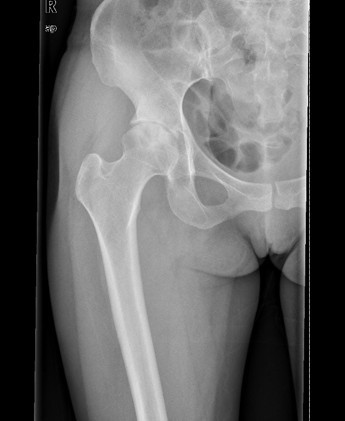

查体:右髋部软组织未见肿胀,双下肢皮肤无破溃,双足趾间皮肤干燥、完好。右髋部后侧轻压痛,双侧足背动脉和胫后动脉搏动正常。 辅查:X线:双侧侧髋臼较浅,髋臼外上方软骨下骨硬化及骨赘,Sharp角右侧约48°、左侧约50°,CE角右侧约20°、左侧约18°,右侧髋关节间隙狭窄,右侧髋臼、股骨头可见囊性改变。

诊断: 1.右侧髋关节发育不良骨关节炎(crowe I型) 2.左侧髋关节发育不良(crowe I型) 3.上呼吸道感染 治疗:排除手术禁忌症后择期手术治疗。